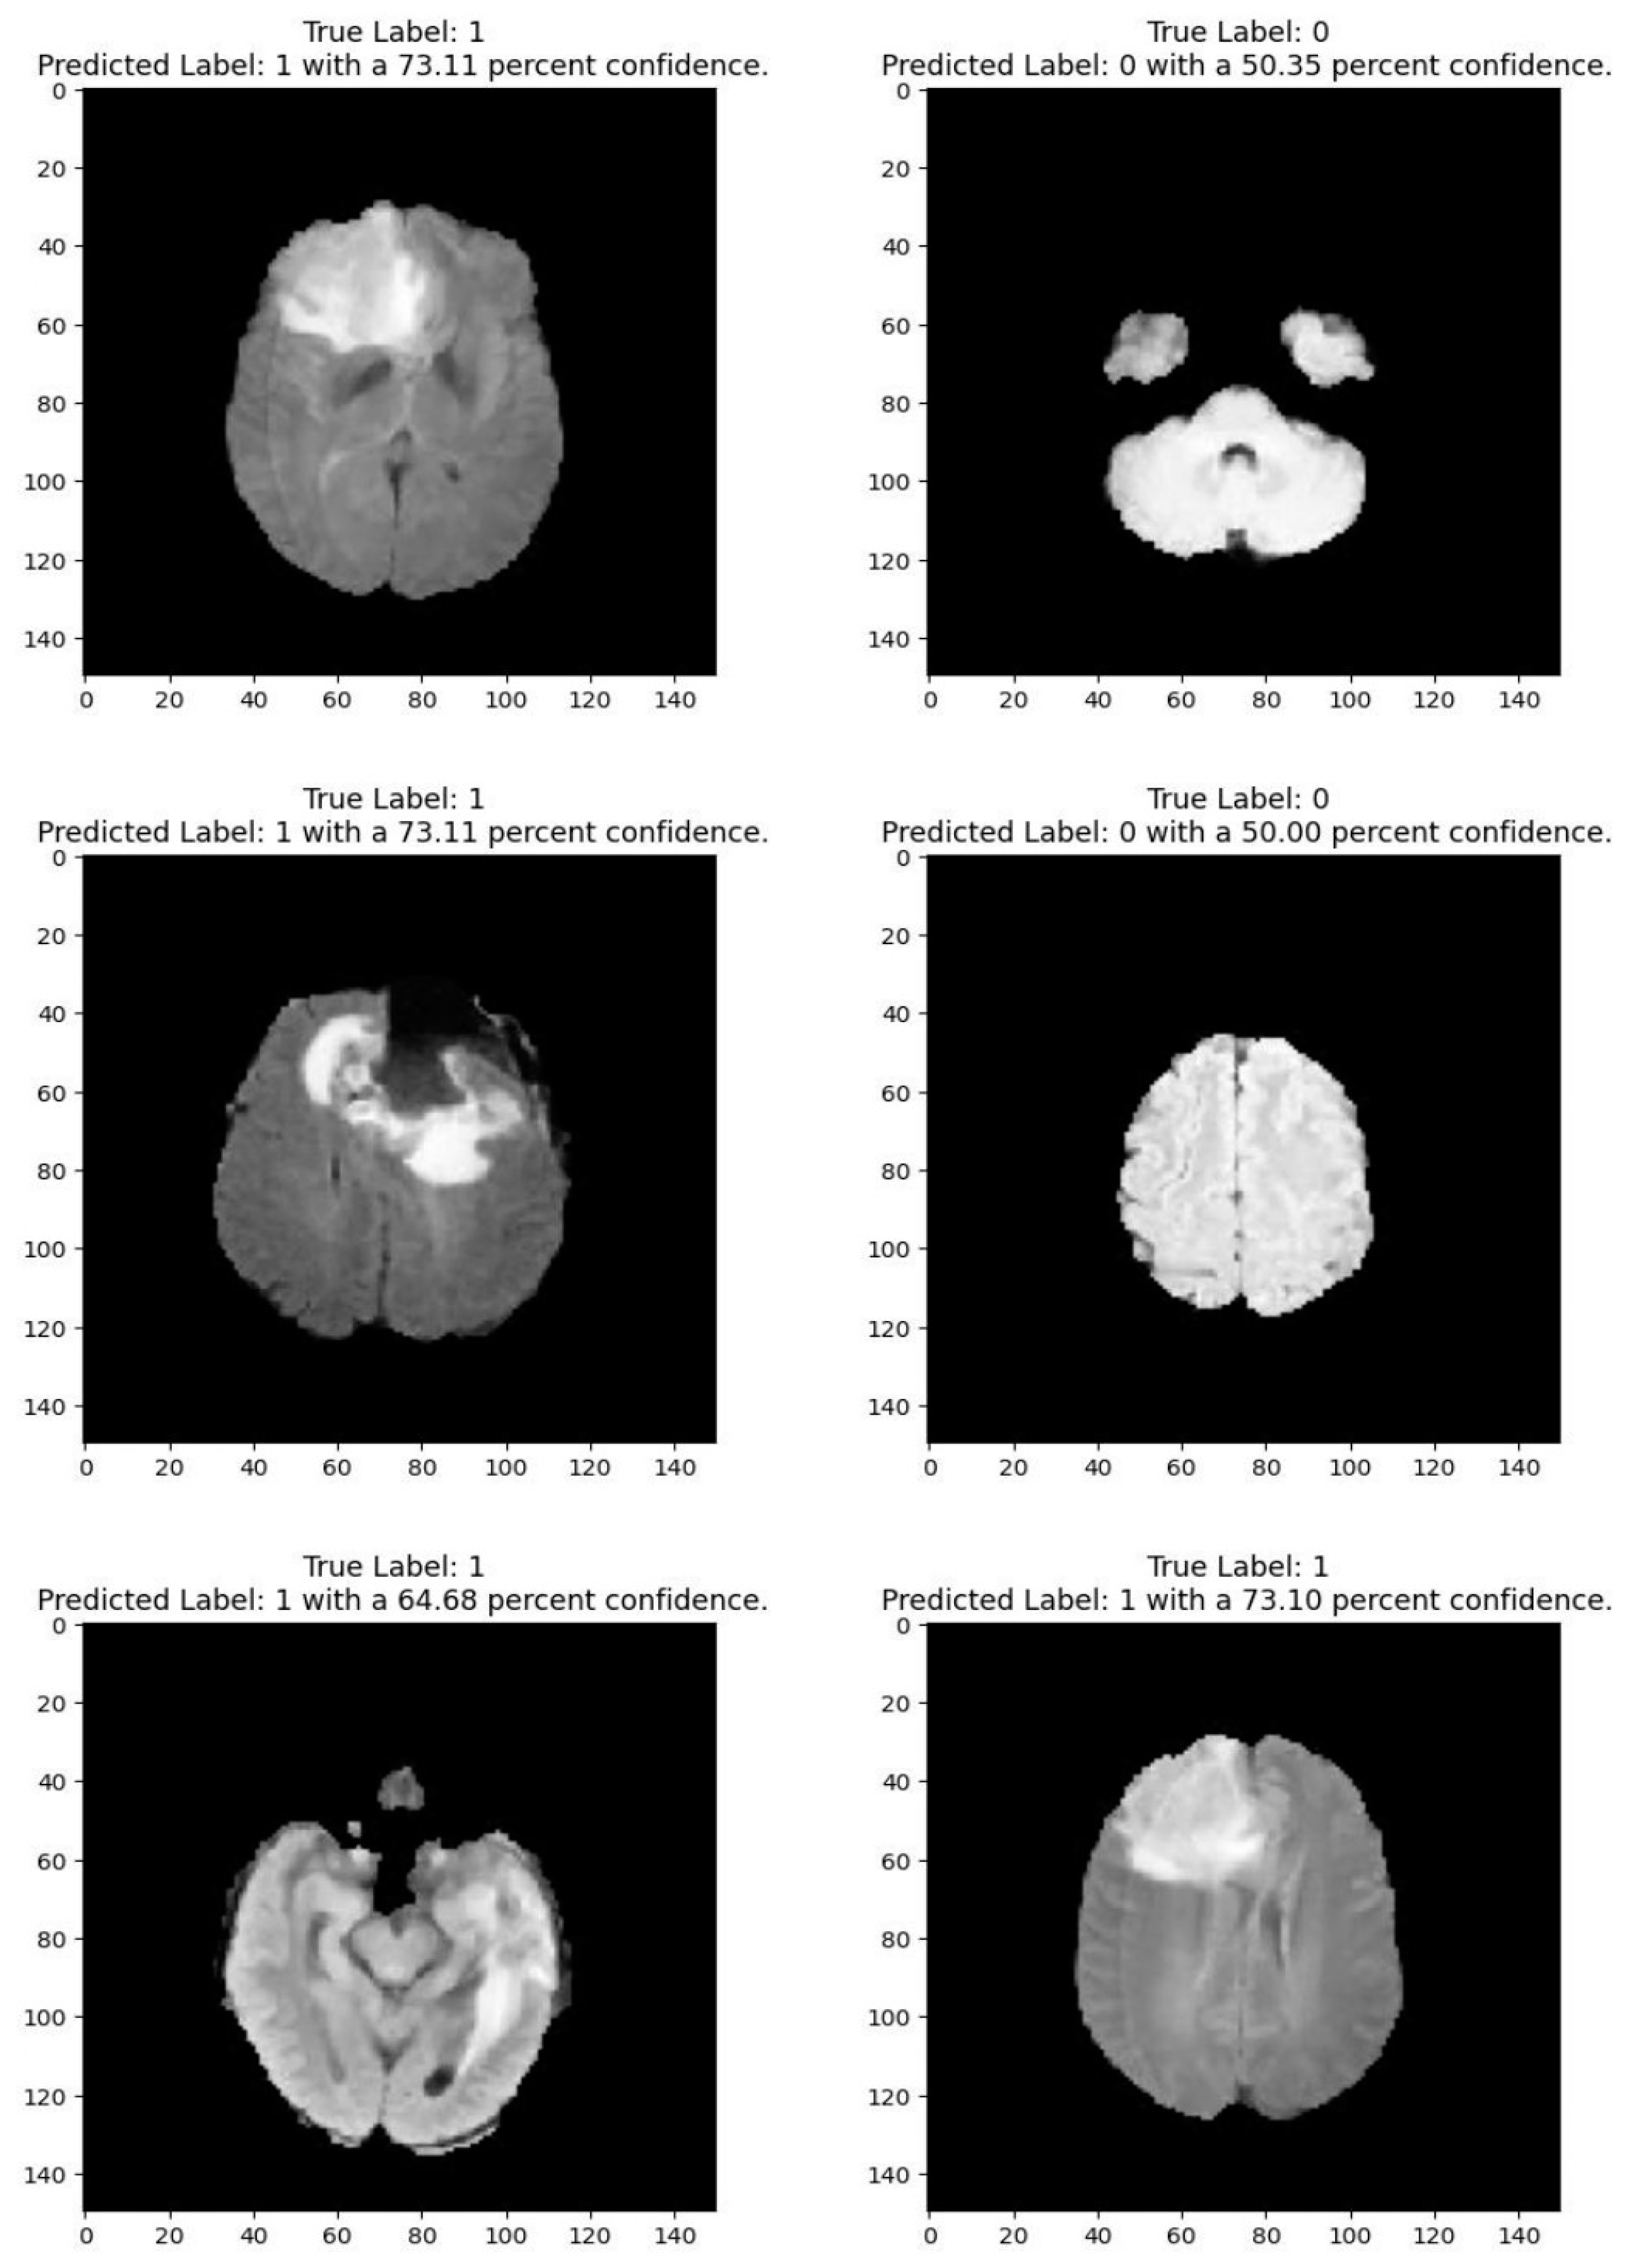

Medical imaging encompasses a diverse array of variations, underscoring the significance of image detection in their interpretation. Our focus was on utilizing MRI scans for the detection of brain tumors. MRI serves as a common modality for both detecting and categorizing brain tumors. In our study, we opted to employ fine-tuned transfer learning models to aid in the identification of brain tumors due to their ability to make precise predictions regarding tumor cells. Figure 9, Figure 10, Figure 11 and Figure 12 display graphical representations of the base model combined with transfer learning operations, and Table 4 presents the corresponding findings. Figure 13, Figure 14, Figure 15 and Figure 16 illustrate the epoch-by-epoch progress of the proposed model, with Table 5 summarizing the associated results. We present a comparison in Table 6 of this study, contrasting the existing research with our proposed approach. Figure 17, Figure 18, Figure 19 and Figure 20 represent the prediction of the model in terms of tumor or non-tumor. The model, named Fine-Tuned Transfer Learning Xception, achieved the highest accuracy of 0.9611, as indicated in the table.

Figure 2 shows that images depicting no tumor typically reveal a serene landscape of brain tissue, characterized by uniform intensity and well-defined anatomical structures. MRI images exhibiting tumors offer a stark contrast. Within these scans, areas of heightened intensity or irregular masses emerge, signaling the presence of pathological growths. These tumors may manifest as distinct lesions, irregular masses, or regions of increased signal intensity, disrupting the otherwise orderly landscape of brain tissue. Notably, the presence of tumors often induces observable changes in adjacent structures, which may appear compressed, displaced, or distorted. By discerning these visual cues, healthcare professionals can effectively differentiate between images with no tumor and those with tumors, facilitating accurate diagnosis and informed treatment decisions for patients

The comparative analysis of the brain tumor detection models highlights the varying performance of different architectures based on methodology and dataset. Traditional deep learning models such as a CNN (92.67% on BraTS 2018) and a DNN (93.10% on BraTS 2014) have shown strong results, while pre-trained architectures like VGG-19 (94.82% on CE-MRI) and Pre-trained CNN (94.58% on CE-MRI) have further improved accuracy by leveraging transfer learning. More advanced hybrid approaches, such as NS-CNN (95.62%) and XG-Ada-RF (95.90%), utilize ensemble techniques to enhance classification performance. The proposed fine-tuned transfer learning models demonstrate competitive and superior performances compared to prior studies. Among them, Xception achieves the highest accuracy of 96.11%, surpassing even ensemble-based techniques. This can be attributed to its depthwise separable convolutions, which optimize feature extraction while reducing computational complexity, making it highly effective for MRI-based classification. Additionally, MobileNetV2 (94.48%), VGG19 (92.46%), and InceptionResNetV2 (92.26%) further validate the effectiveness of fine-tuned transfer learning.

The clinical applicability of the proposed model lies in its high accuracy, generalizability, and efficiency in brain tumor detection, making it a valuable tool for medical diagnosis. With the Xception-based model achieving a 96.11% accuracy, it demonstrates a strong potential for assisting radiologists in identifying brain tumors from MRI scans with high precision and minimal error rates. This can significantly reduce diagnostic time, aiding in early detection and treatment planning.